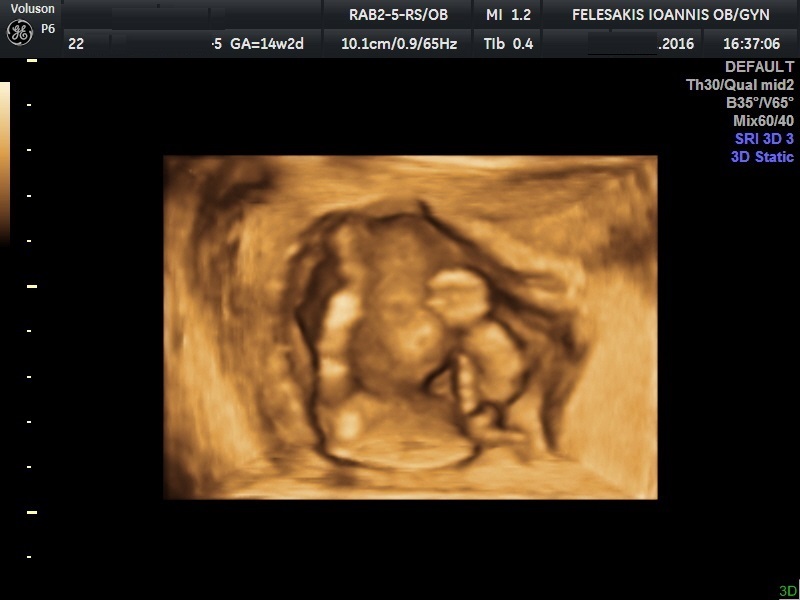

Είναι μία εντυπωσιακή απεικόνιση του εμβρύου μέσα στο "δικό του χώρο". Υπάρχει η δυνατότητα στατικής απεικόνισης όσο και "realtime".Τα αποτελέσματα απεικονίζονται σε ψηφιακή μορφή και αποτελούν επί της ουσίας τη πρώτη οπτική επαφή του ζευγαριού με το έμβρυο.